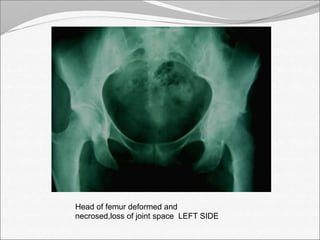

Head of femur deformed and

necrosed,loss of joint space LEFT SIDE

Head of femurdeformed and necrosed,loss of joint space LEFT SIDE